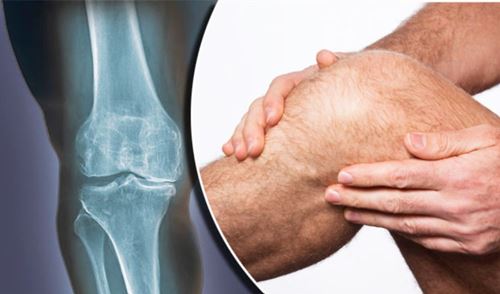

2- İltihapsız romatizmal hastalıklar: Bu romatizmaların en önemlisi halk arasında kireçlenme olarak bilinen sıklıkla diz, kalça, bel ve boyun eklemlerini tutan artrozdur. Bu hastalığın nedenleri yaşlanma, obezite ve genetik yatkınlıktır. Artrozda eklemde iltihap yoktur. Buna karşılık kıkırdakta incelme ve kaybolma, kemikte ise aşınma ve çıkıntılar vardır. Travmalar (kaza, düşme, darbe), mesleki zorlanmalar, mekanik nedenler, fibromiyalji sendromu, metabolik ve psikolojik bozukluklar iltihapsız romatizmanın en önemli nedenleridir. Bir diğer iltihapsız romatizmal hastalık fibromiyalji sendromudur. Sıklıkla kadınları etkileyen bu hastalık 20-50 yaş arasında görülmektedir. Yaygın vücut ağrısı, dinlendirmeyen uyku, kısa süreli sabah tutukluğu, depresif semptomlar, anksiyete, baş ağrısı bu hastalığın belirtileri arasındadır. Fibromiyalji tanısında kan tahlilleri, diğer olası hastalıkları (demir eksikliği, D vitamini eksikliği, tiroid hastalığı) dışlamak açısından yardımcıdır.

- Artroz (Kireçlenme)